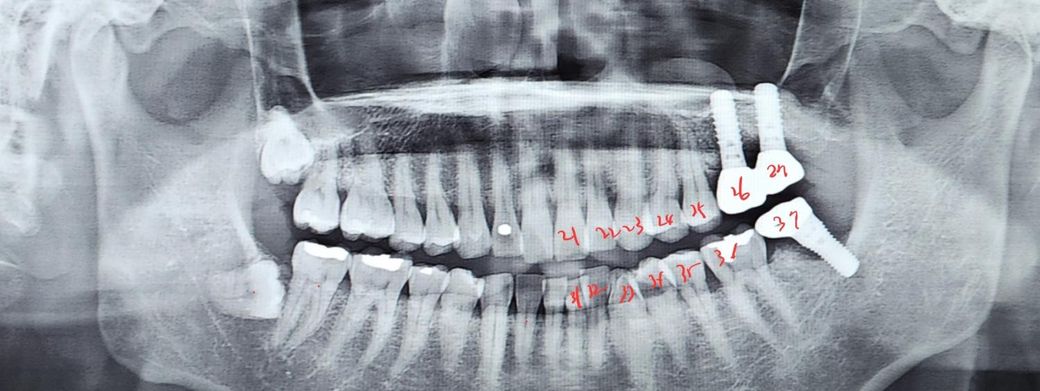

임플란트 염증이 발생해 뼈가 많이 녹았다 해서 37번 치아 제거후 다시 심지 않고 27번은 밀봉하고 26번과 36번으로 저작할수 있게 하려고 합니다 밀봉했을때 27번은 문제 없는지 기능상 문제가 없을지 궁금합니다

이런 경우 #37임플란트 제거하고 다시 임플란트 심지 않는 경우 종종 있습니다. 이렇게 해도 씹는데는 큰 문제없습니다.

임플란트를 밀봉한다는게 보철물을 제거하고 임플란트 나사를 묻어 놓는다는 의미인거라면 그렇게 하셔도 크게 문제가 되진 않습니다.

치열을 상실했을 경우 해당 치아에 가해질 수 있는 교합력이 다른 치아에 가해지게되어 해당 지아가 수명이 줄 수 있습니다. 치열을 상실했다면 가능한 치아를 수복하는 것이 좋을 수 있습니다